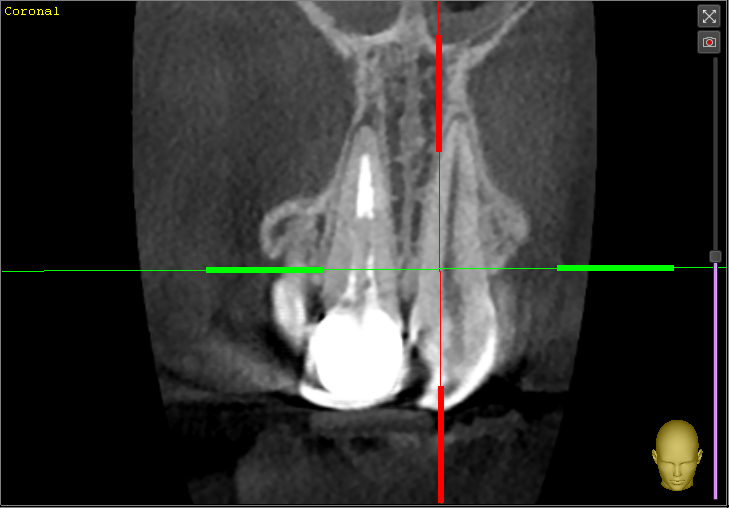

Lex2023 Опубликовано 19 июня, 2023 Автор Поделиться Опубликовано 19 июня, 2023 @IvanK Здравствуйте. Сегодня сделал 3д снимок, сказали все хорошо (воспаления нет, канал запломбирован хорошо, сам корень без трещин и т.п), соседние зубы тоже в отличном состоянии , но боль не проходит.Коронку снимать смысла нет говорят. Попросил результат сканирования, скинули вот это.Если можете, посмотрите пожалуйста, не знаю уже к кому обращаться. 789686638_20230619-115700-142_.zip Ссылка на комментарий

АнтонТЛТ Опубликовано 20 июня, 2023 Поделиться Опубликовано 20 июня, 2023 Канал не до конца запломбирован Ссылка на комментарий

Lex2023 Опубликовано 21 июня, 2023 Автор Поделиться Опубликовано 21 июня, 2023 (изменено) 20.06.2023 в 14:09, АнтонТЛТ сказал: Канал не до конца запломбирован @АнтонТЛТ Может можно медикаментозно это вылечить, врач видел что не до конца запломбирован канал, но сказал что из-за него не может болеть, пломбировали задолго до установки коронки, больше 10-ти лет точно прошло. А если и перелечивать реально эту же коронку сохранить? Изменено 21 июня, 2023 пользователем Lex2023 Ссылка на комментарий